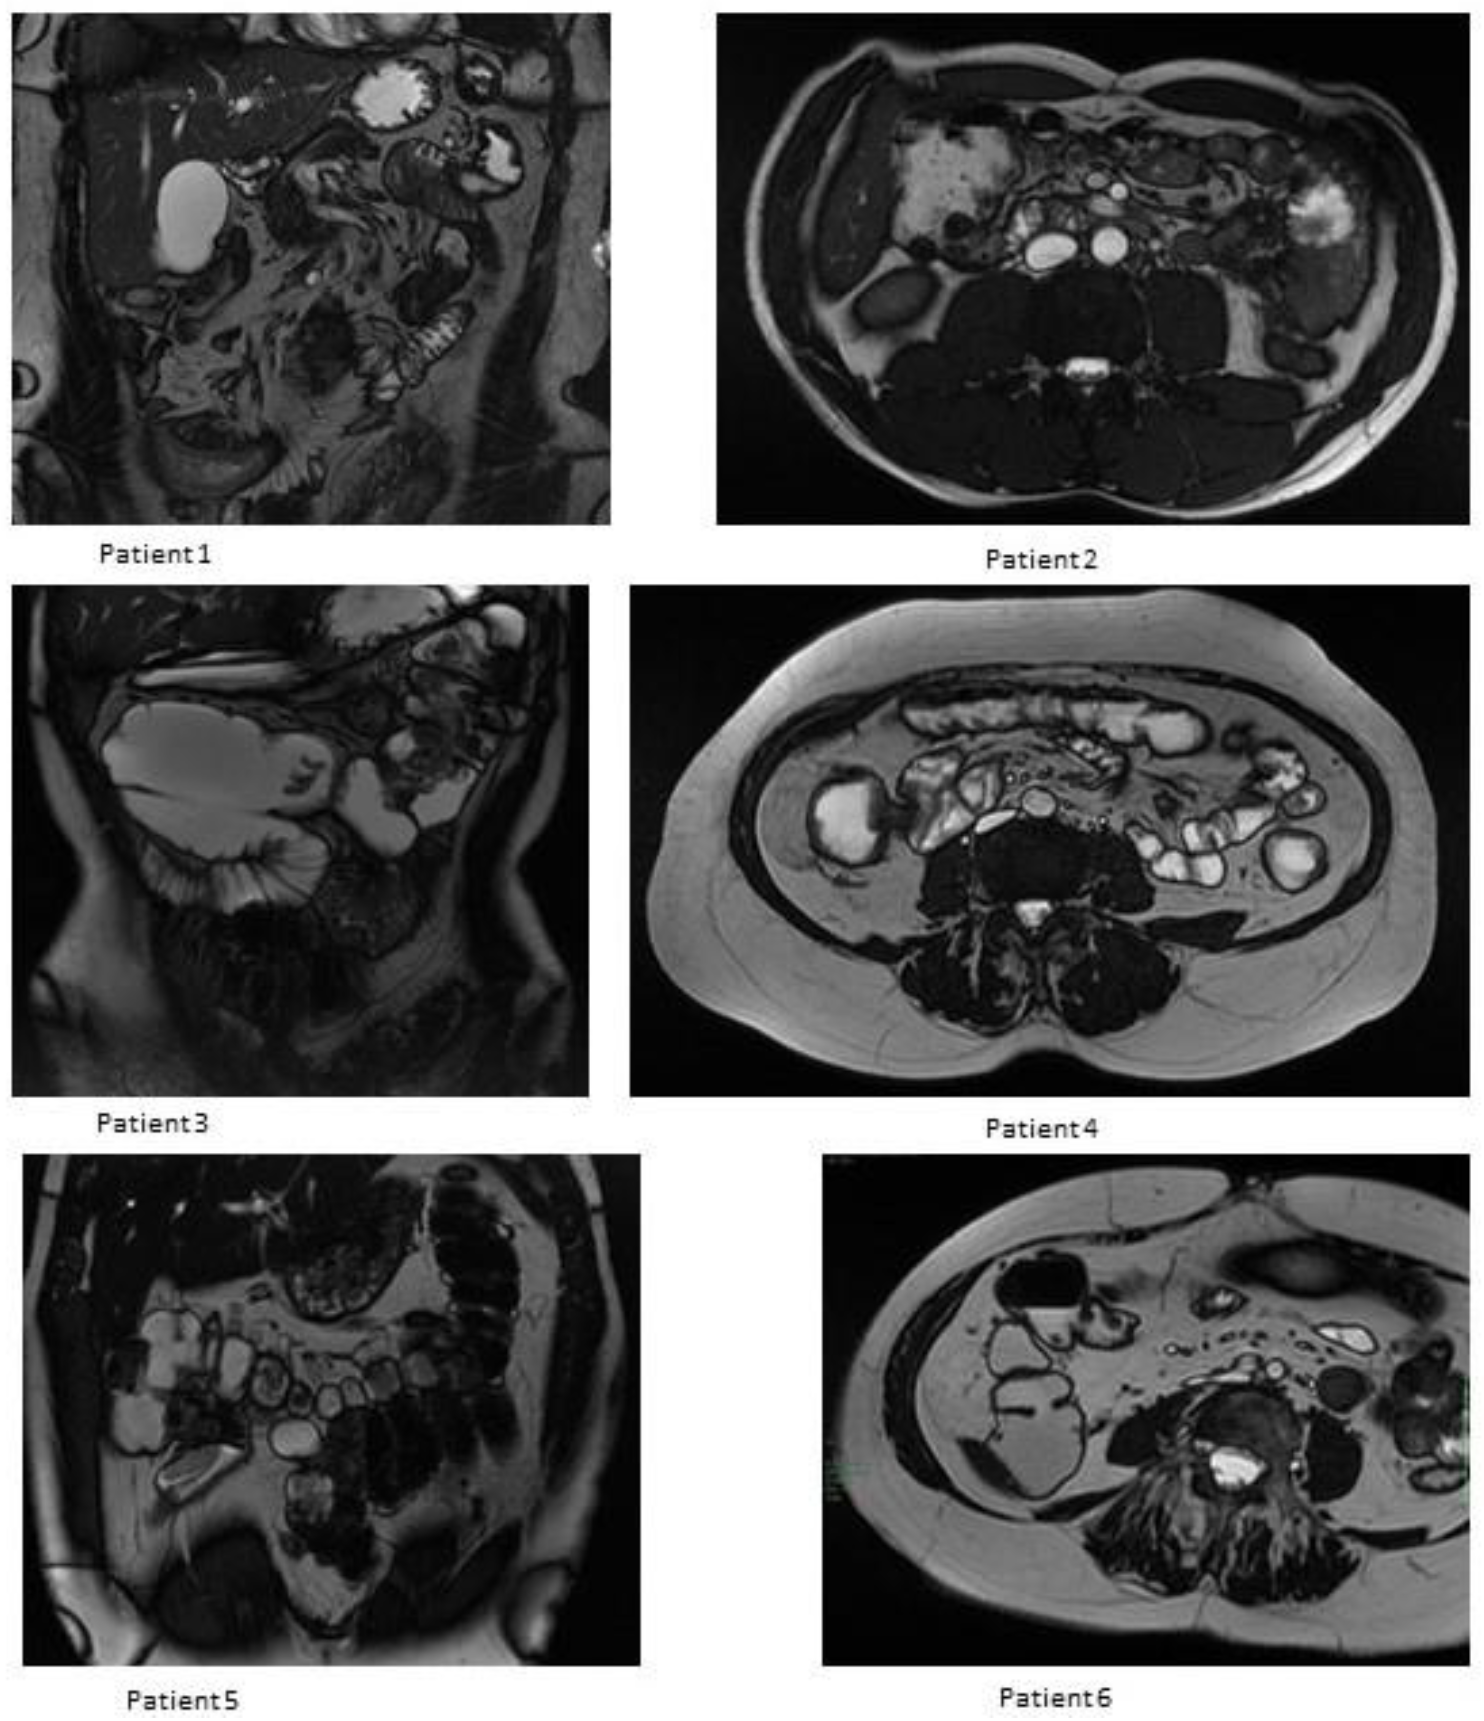

3.3. MRE Evaluation

| Female | 41 | 9 | Inflammatory stenosis; Active penetrating disease | A3/L3/B3p | ADA | No | 50 | 4 | 0 (10) | i4 (32) | T+: i, lc; E+: i, lc (19) | 33 | Yes (10) |

| Male | 26 | 1 | Inflammatory stenosis | A2/L3/B3 | IFX | No | 27 | 6 | i1 (12) | i0(26) | T−; E+: i (13) | 58 | No (1) |

| Female | 31 | 6 (1st resection) 16 (2nd resection) | Inflammatory stenosis; Active penetrating disease | A2/L3/B3p | IFX; AZA | Yes | 57 | 10 | 0 (8) | 0 (32) | T−; E− (17) | 62 | No (1) |

| Female | 52 | 11 | Inflammatory stenosis | A3/L1/B2 | ADA | No | 63 | 6 | 0 (12) | i0(33) | T+: lc, sc E+: lc (52) | 64 | No (1) |

| Male | 53 | 2 | Fibrotic stenosis | A3/L1/B2 | IFX | No | 54 | 12 | 0 (8) | i1 (25) | T−; E− (14) | 45 | No (4) |

| Female | 62 | 2 | Inflammatory stenosis; | A3/L3/B2 | ADA | No | 64 | 6 | 0 (8) | n.a. | T−; E+: i (29) | 39 | No (2) |